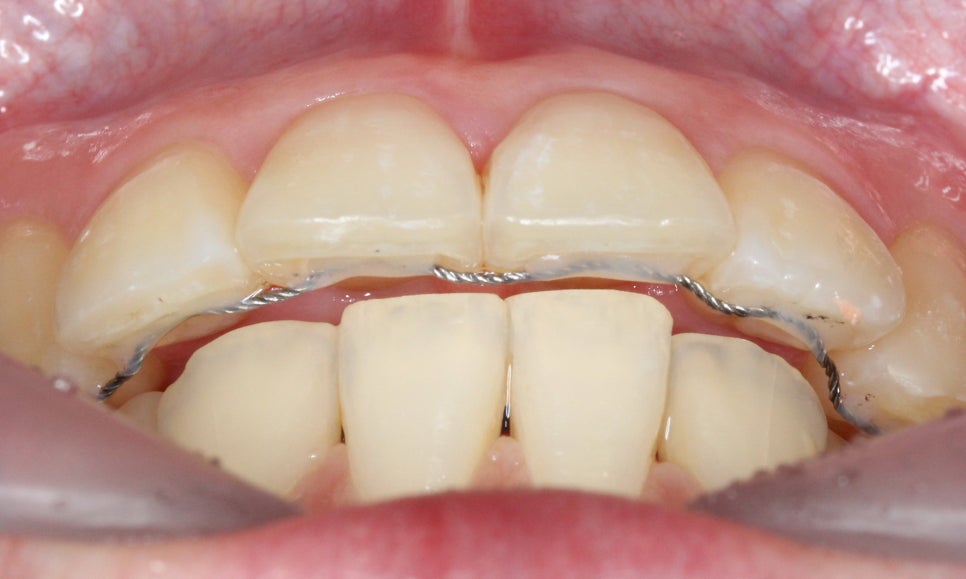

대치동치과 돌출입 교정 전 모습입니다.

전치부의 치아 배열을 보면

앞니가 튀어나와 있고 상하악의

정중선이 변위된 모습을 확인할 수 있는데요,

치아의 중심이 잘 맞지 않는 경우

어금니 부분이 어긋나게 교합되거나

턱 부분의 교합이 좋지 않은 상황일 수 있습니다.